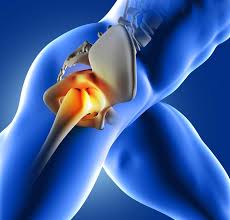

What Are The Symptoms Of Bone Cancer In Your Hip - Lower Back And Hip Pain Causes Treatment And When To See A Doctor - Discover 10 common bone cancer symptoms at 10faq health and stay better informed to make healthy living decisions.. When a bone tumor grows, it presses on healthy bone tissue. Even though swelling can occur with bone cancer in the hip, swelling is often the symptom of something else. Cancer in bone can cause intermittent or progressively severe localized bone pain where the cancer is in the bone. You will also receive emails from mayo clinic on the latest about cancer news. Bone cancer is a fairly rare disease, so if you've developed bone pain, don't jump to conclusions.

Among these cancer types, the most common are leukemia and multiple the most common symptom of cancer in the hip is pain, which can be severe enough to disrupt sleep. It is the most severe symptom of blood cancer because of low blood platelets. There are four main types of primary bone cancer that can affect the hip. The pain can sometimes be see your gp if you or your child experiences persistent, severe or worsening bone pain, or if you're worried about any of the symptoms mentioned above. Symptoms of escherichia coli become an expanded clinical picture of intestinal dysbiosis: In rare cases, these can also. Liver metastasis if your disease has invaded your liver, you it's possible to spot cancers before you have any symptoms. Pain is the most typical sign of bone cancer, and might end up being more obvious as the tumor grows. Bone cancer develops in the skeletal system and destroys tissue. Learn more about the symptoms, risk factors, diagnosis, types, treatment, and outlook for bone cancer. Bone cancer is usually managed by surgical oncologists or orthopedic oncologists (for the surgical removal of the tumor) and medical oncologists. Hip cancer can also originate in the bone marrow, cartilage, and soft tissue. Osteochondroma is the most common.

It often happens in people under age 20. Learn about bone cancer symptoms and treatments. When a bone tumor grows, it presses on healthy bone tissue. Symptoms of bone cancer in the hip area: Discover 10 common bone cancer symptoms at 10faq health and stay better informed to make healthy living decisions.